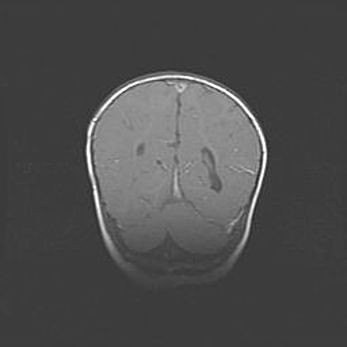

Лейкомаляция с кистозно-глиозной дегенерацией головного мозга.

Возраст: 2 месяца 25 дней

Вес: 6400 г

Окружность головы: 40 см

Срок гестации: 41 неделя

Лейкомаляцию относят к ишемически-гипоксическим повреждениям головного мозга, диагностируемым у новорожденных. При лейкомаляции в головном мозге обнаруживают очаги некроза, возникшие после тяжелой гипоксии и нарушения кровотока. В процессе морфогенеза очаги проходят три стадии: 1) развития некроза, 2) резорбции и 3) формирования глиозного рубца или кисты. Перивентрикулярная лейкомаляция (ПЛ) встречается примерно в 12% случаев среди новорожденных, обычно – у недоношенных детей, причем, частота ее зависит от массы, с которой младенец появился на свет. Наибольшее число малышей страдает лейкомаляцией, если масса при рождении 1500-2500 г.